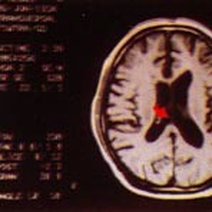

脑动脉瘤是颅内动脉血管的异常瘤状突起。脑动脉瘤不破裂,一般病人没有明显症状,如果破裂出血,常表现为蛛网膜下腔出血,病人可以出现剧烈的头痛,恶心呕吐,甚至出现...11216人收听

- 数字减影血管造影技术,颅内动脉瘤介入治疗,湘雅护理学院,颅内动脉瘤,颅内动脉瘤系指脑动脉壁的异常膨出部分,是引起自发性蛛网膜下腔出血的最常见原因。病因-尚不甚清楚,但以先天性动脉瘤占大部分。任何年龄可

- 动瘤DavidSLiebeskind1引1.1景动瘤是有破倾向的管结构的病理性局灶性扩张。些管异常常根据假定的病因分类。囊状、浆果状或先天性动瘤占全动瘤的90